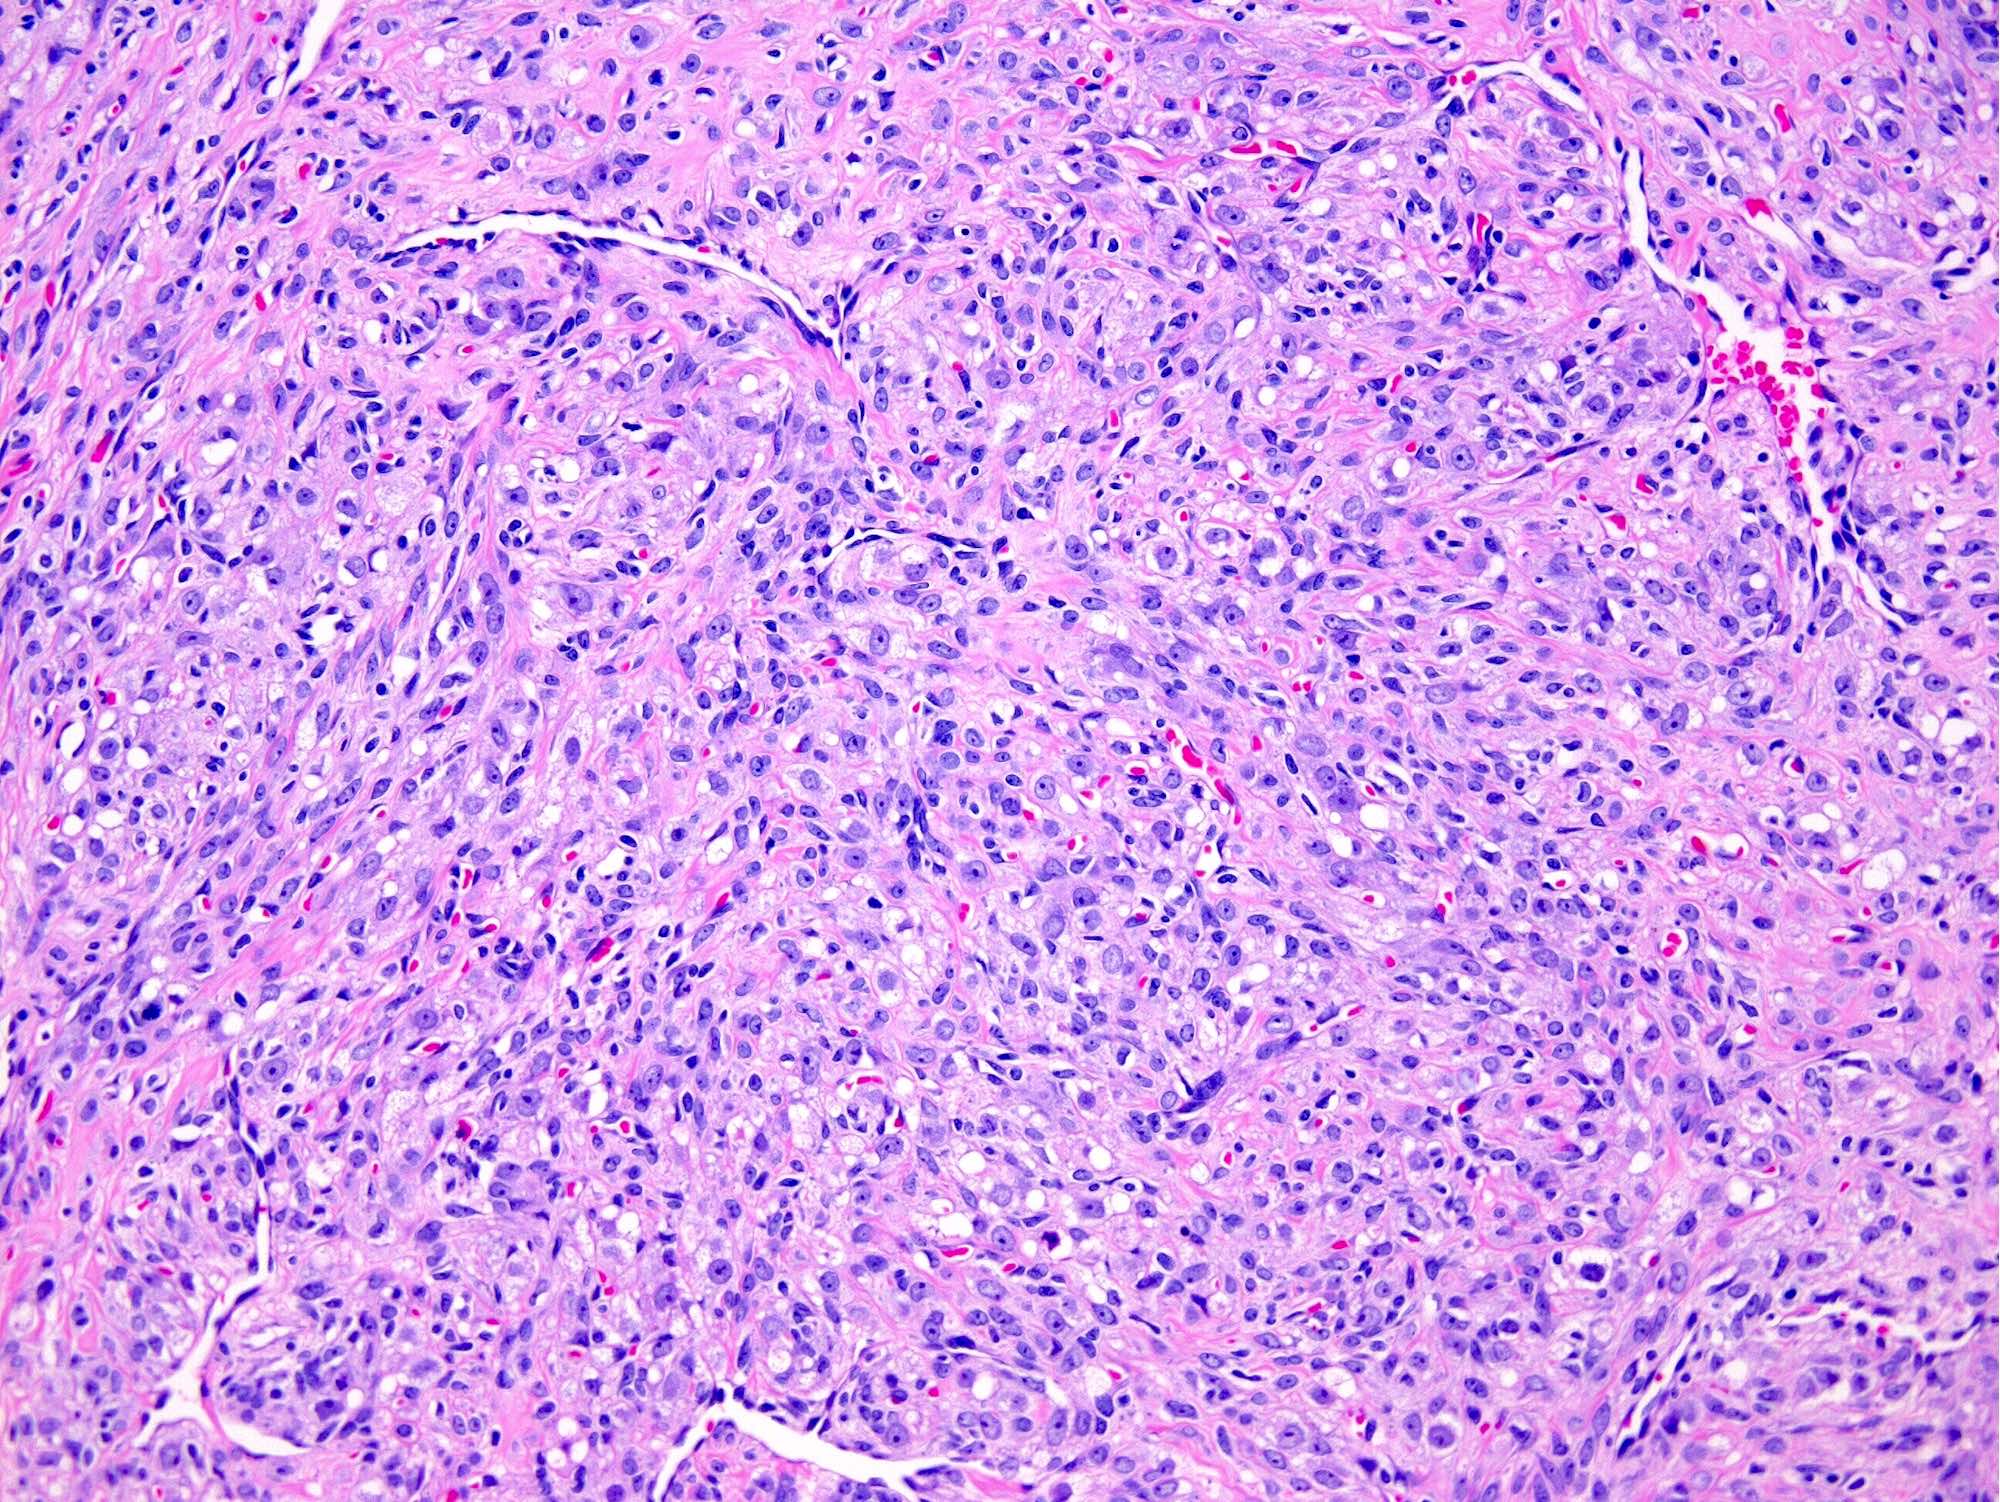

- Thin, dilated and branching hemangiopericytoma-like vasculature is often conspicuous in both components

- Pseudolobules comprised of a jumbled admixture of epithelioid (lutein) and spindled cells with minimal atypia

- Epithelioid cells: round nuclei with prominent nucleoli, vesicular chromatin and clear to vacuolated cytoplasm

- Spindled cells: elongated nuclei with indistinct nucleoli, bland chromatin and scant eosinophilic cytoplasm

- Typically round to ovoid but may show angulation if edema is striking

- Hypocellular areas can be edematous, collagenous (variably keloid-like) or myxoid

- References: Cancer 1973;31:664, Histopathology 2022;80:360

Microscopic (histologic) images